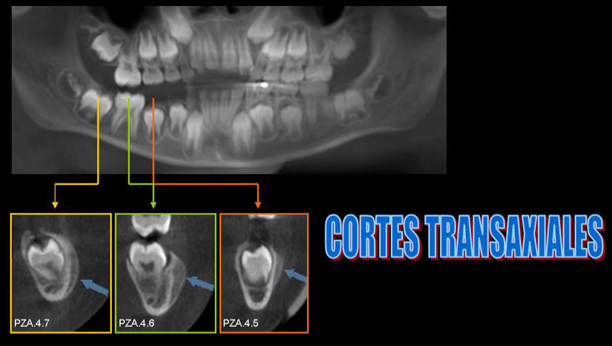

Paciente masculino 8 años de edad, es referido a la consulta para la evaluación con tomografía volumétrica por presentar un aumento de volumen indurado en la zona molar inferior derecha. En la radiografía panorámica notamos la ausencia de la piezas 8.4, 8.5 y la pieza 4.6 en infraoclusión. Se realiza estudio con tomografía volumétrica (Picasso E-WOO), se grafican cortes axiales, coronales y transaxiales que muestran a nivel de la pieza 4.6 ensanchamiento del espacio pericoronario hacia vestibular y reacción periostal que se extiende hacia la pieza 4.5 y 4.7.